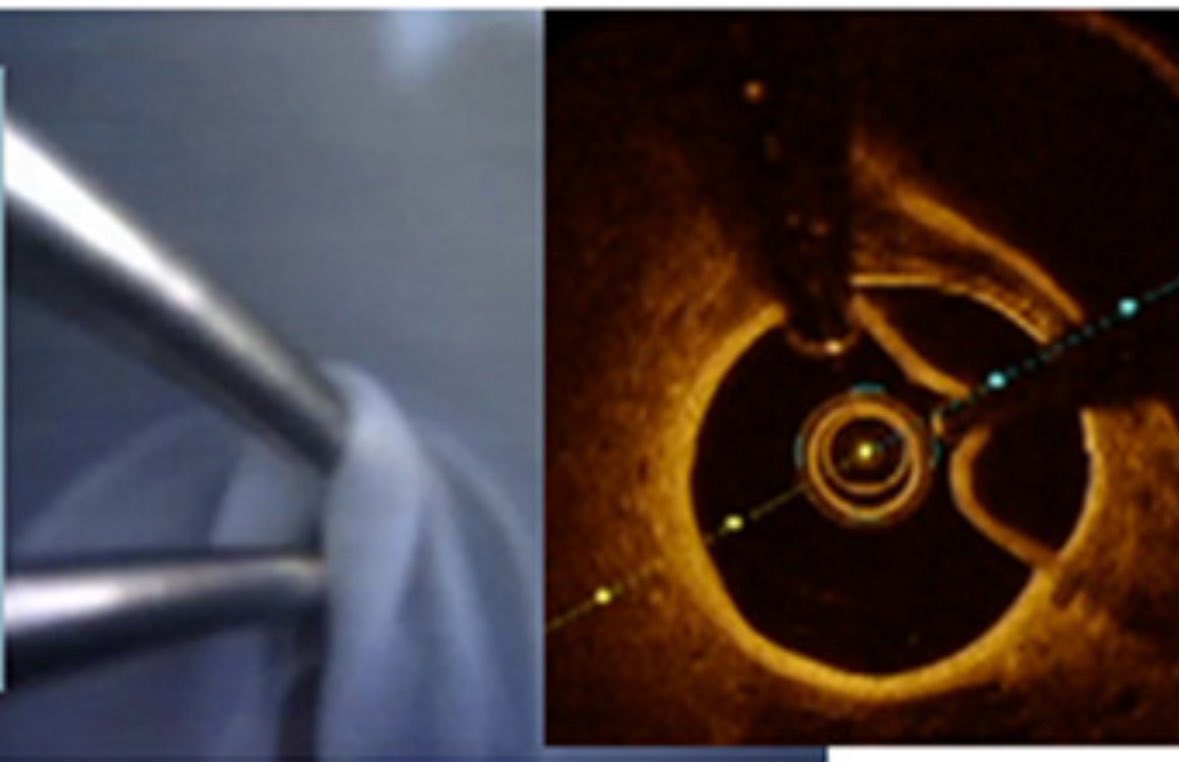

Presenting our new methods of bifurcation stenting in TCT 2025: IM-CRUSH ✅7F guide compatible with Altaview ✅real time IVUS guidance ✅minimal protrusion into LM carina ✅adequate ostial coverage #bifurcationstenting #pci #imcrush #Tct2025 @drcleung

✅7F guide compatible with Altaview

✅real time IVUS guidance

✅minimal protrusion into LM carina

✅adequate ostial coverage